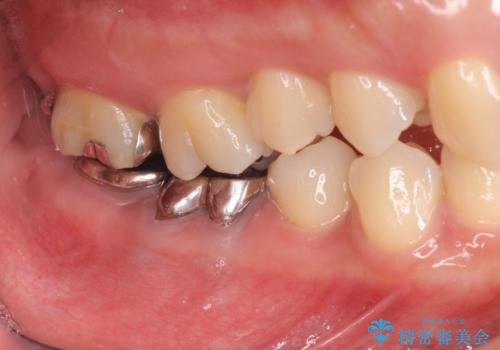

- 「笑った時に目立つ奥歯の銀歯を外して白くしたい。」と希望され来院されました。

金属のクラウンは薄く加工しても壊れないことがメリットですが、セラミッククラウンを装着するにはスペースが少なすぎ、このまま治療を進めると外れやすく壊れ易いセラミッククラウンの設計となるため、歯周外科を行い狭小なスペースの拡大を行うこととしました。

- 38.5万円(セラミッククラウン×2・仮歯×2 歯周外科手術)費用は治療当時の料金となります